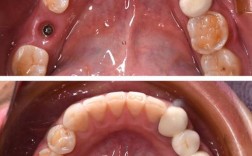

| 种植手术 | 局部麻醉后,在牙槽骨植入种植体,微创技术(如即刻种植)可缩短手术时间,缝合伤口 | 30-90分钟 | 术后24小时内避免刷牙、漱口,遵医嘱服用抗生素 |

| 戴牙冠 | 种植体骨结合(3-6个月后),通过3D口扫制作牙冠,安装并调整咬合关系 | 1-2周 | 初期避免用种植牙咬过硬食物(如坚果、骨头),适应后可正常咀嚼 |